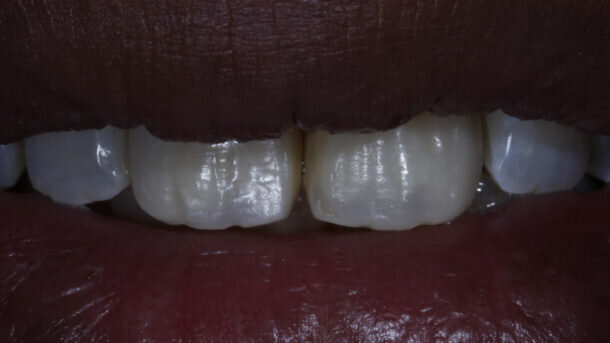

Presenting a case of a 22 yr old male, who reported to our dental office with fractured Maxillary Central incisors many years ago [Figures 1 and 2]. On examination both Maxillary Central incisors had fractures with pulp exposures. IOPAR showed large peri-apical lesions in both teeth. There was no mobility seen in either teeth, but discolouration was seen in both. Non-surgical Endodontic treatment followed by Bleaching and Direct composite restorations (2 weeks post bleaching) were planned.

The figures show the clinical work flow involved. In the 1st appointment Oral prophylaxis, oral hygiene instructions were followed by an impression that was sent to the lab for a wax up [Fig 3 and 4]. In the subsequent appointments, Endodontic treatment was followed by Intra and extra coronal office bleaching using the Pola office bleaching kit. After two weeks, the shade stabilised post bleaching. Shade selection, rubber dam isolation and preparation was done on both the teeth to receive Direct composite veneers so as to close the midline diastema as well as correct the fractured teeth and the slight mal-alignment. Controlled Body Thickness (CBT) technique of layering was used with 3M Z350XT shades - Dentin shades A3, A2 and Enamel shades A2, clear translucent [Figures 5 to 11]. This was followed by the Finishing and polishing protocol as described in the figures.